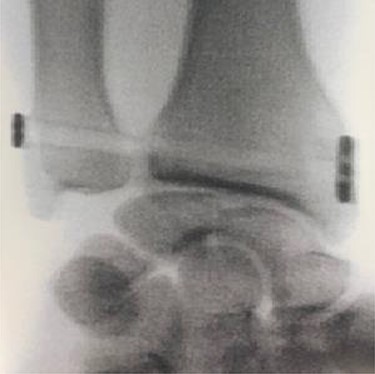

As emergency treatment, we realized a closed reduction of the elbow dislocation under general anaesthesia with X-ray control, the limb was stabilized in a posterior brachiopalmar splint. A computed tomography (CT) confirmed the stage 2 coronoid process fracture and a partial radial head fracture, the PRUJ dislocation was also demonstrated (Fig. 2). The DRUJ and PRUJ dislocations were suggestive of a complete disruption of the interosseous membrane. We managed a surgical treatment the second day of admission. A Kaplan approach was used to reduce the PRUJ dislocation, the annulate ligament was repaired and the radial head fracture was evaluated, as the detached fragment was <20% of the radial head circumference, no fixation was necessary. The lateral collateral ligament (LCL) and the common extensor muscle were repaired. The elbow testing objected a stable elbow from −30° of extension to complete flexion. According to that elbow stability status and the coronoid fracture stage, we decided a conservative treatment for the anteromedial coronoid fracture. Closed reduction of the DRUJ was achieved but it was instable, a fixation with a TightRope was used (Fig. 3). The stability was rechecked and upgrade of the stable range of motion (ROM) was assessed, the elbow was now stable from −20° extension to complete flexion. A sling was used for comfort for 2 weeks postoperatively with physiotherapy and ROM exercises initiated early.

Anteroposterior X-ray of the wrist showing the DRUJ reduction and the TightRope stabilization.